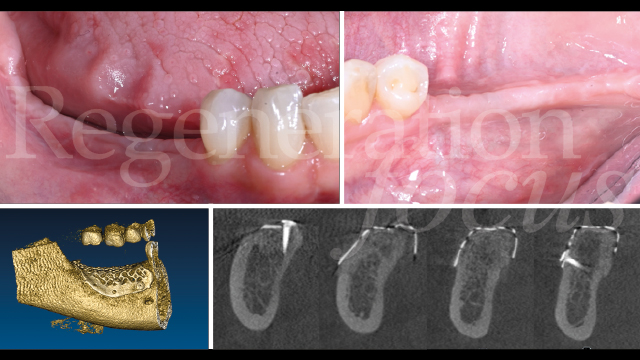

Una paziente di 44 anni, non fumatrice e in buone condizioni di salute generale, si è presentata riferendo significative difficoltà masticatorie, nel quarto quadrante, conseguenti alla perdita del ponte 45-47 per complicanze endodontico-protesiche. L’anamnesi medica non rivelava patologie sistemiche di rilievo né assunzione di farmaci che potessero interferire con i processi di guarigione ossea. L’esame intraorale evidenziava una discreta atrofia della cresta alveolare edentula con collasso vestibolo-linguale dei tessuti molli (Fig. 1). Gli elementi dentari adiacenti presentavano condizioni parodontali stabili. L’analisi radiografica tridimensionale, mediante CBCT, ha permesso una valutazione dettagliata del deficit osseo (Fig. 2). Dopo discussione delle diverse opzioni terapeutiche, inclusa la possibilità di impianti corti, si è optato per una rigenerazione ossea guidata mediante mesh customizzata.

Il follow-up a 2 e 4 settimane ha documentato la guarigione per prima intenzione. A 6 mesi, la CBCT ha evidenziato eccellente integrazione dell’innesto con ottimale densità ossea (Fig. 10). La seconda fase chirurgica ha previsto la rimozione della mesh e l’inserimento simultaneo di due impianti tissue level (3.7 x 10 mm plat. 3.7 in sede 45; 3.7 x 8 mm plat. 4.5 in sede 47) caratterizzati da un design transmucoso concavo di 1.8 mm con superficie anodizzata (Matrix Line, TRI Dental Implants) (Fig. 11). Il torque di inserimento di 45 Ncm ha confermato l’ottima qualità ossea.

Il follow-up clinico e radiografico a 12 mesi ha documentato eccellente stabilità del risultato ottenuto. L’analisi radiografica non ha evidenziato rimodellamento osseo marginale né segni di radiolucenza peri-implantare o alterazioni della trabecolatura ossea (Fig. 16). I parametri clinici peri-implantari hanno mostrato profondità di sondaggio inferiori a 4 mm e assenza completa di sanguinamento al sondaggio. L’analisi del fenotipo tissutale ha documentato incremento significativo dello spessore mucoso e l’analisi del microbioma ha rivelato composizione batterica compatibile con la salute peri-implantare e il mantenimento dell’eubiosi (Figg. 17,18).